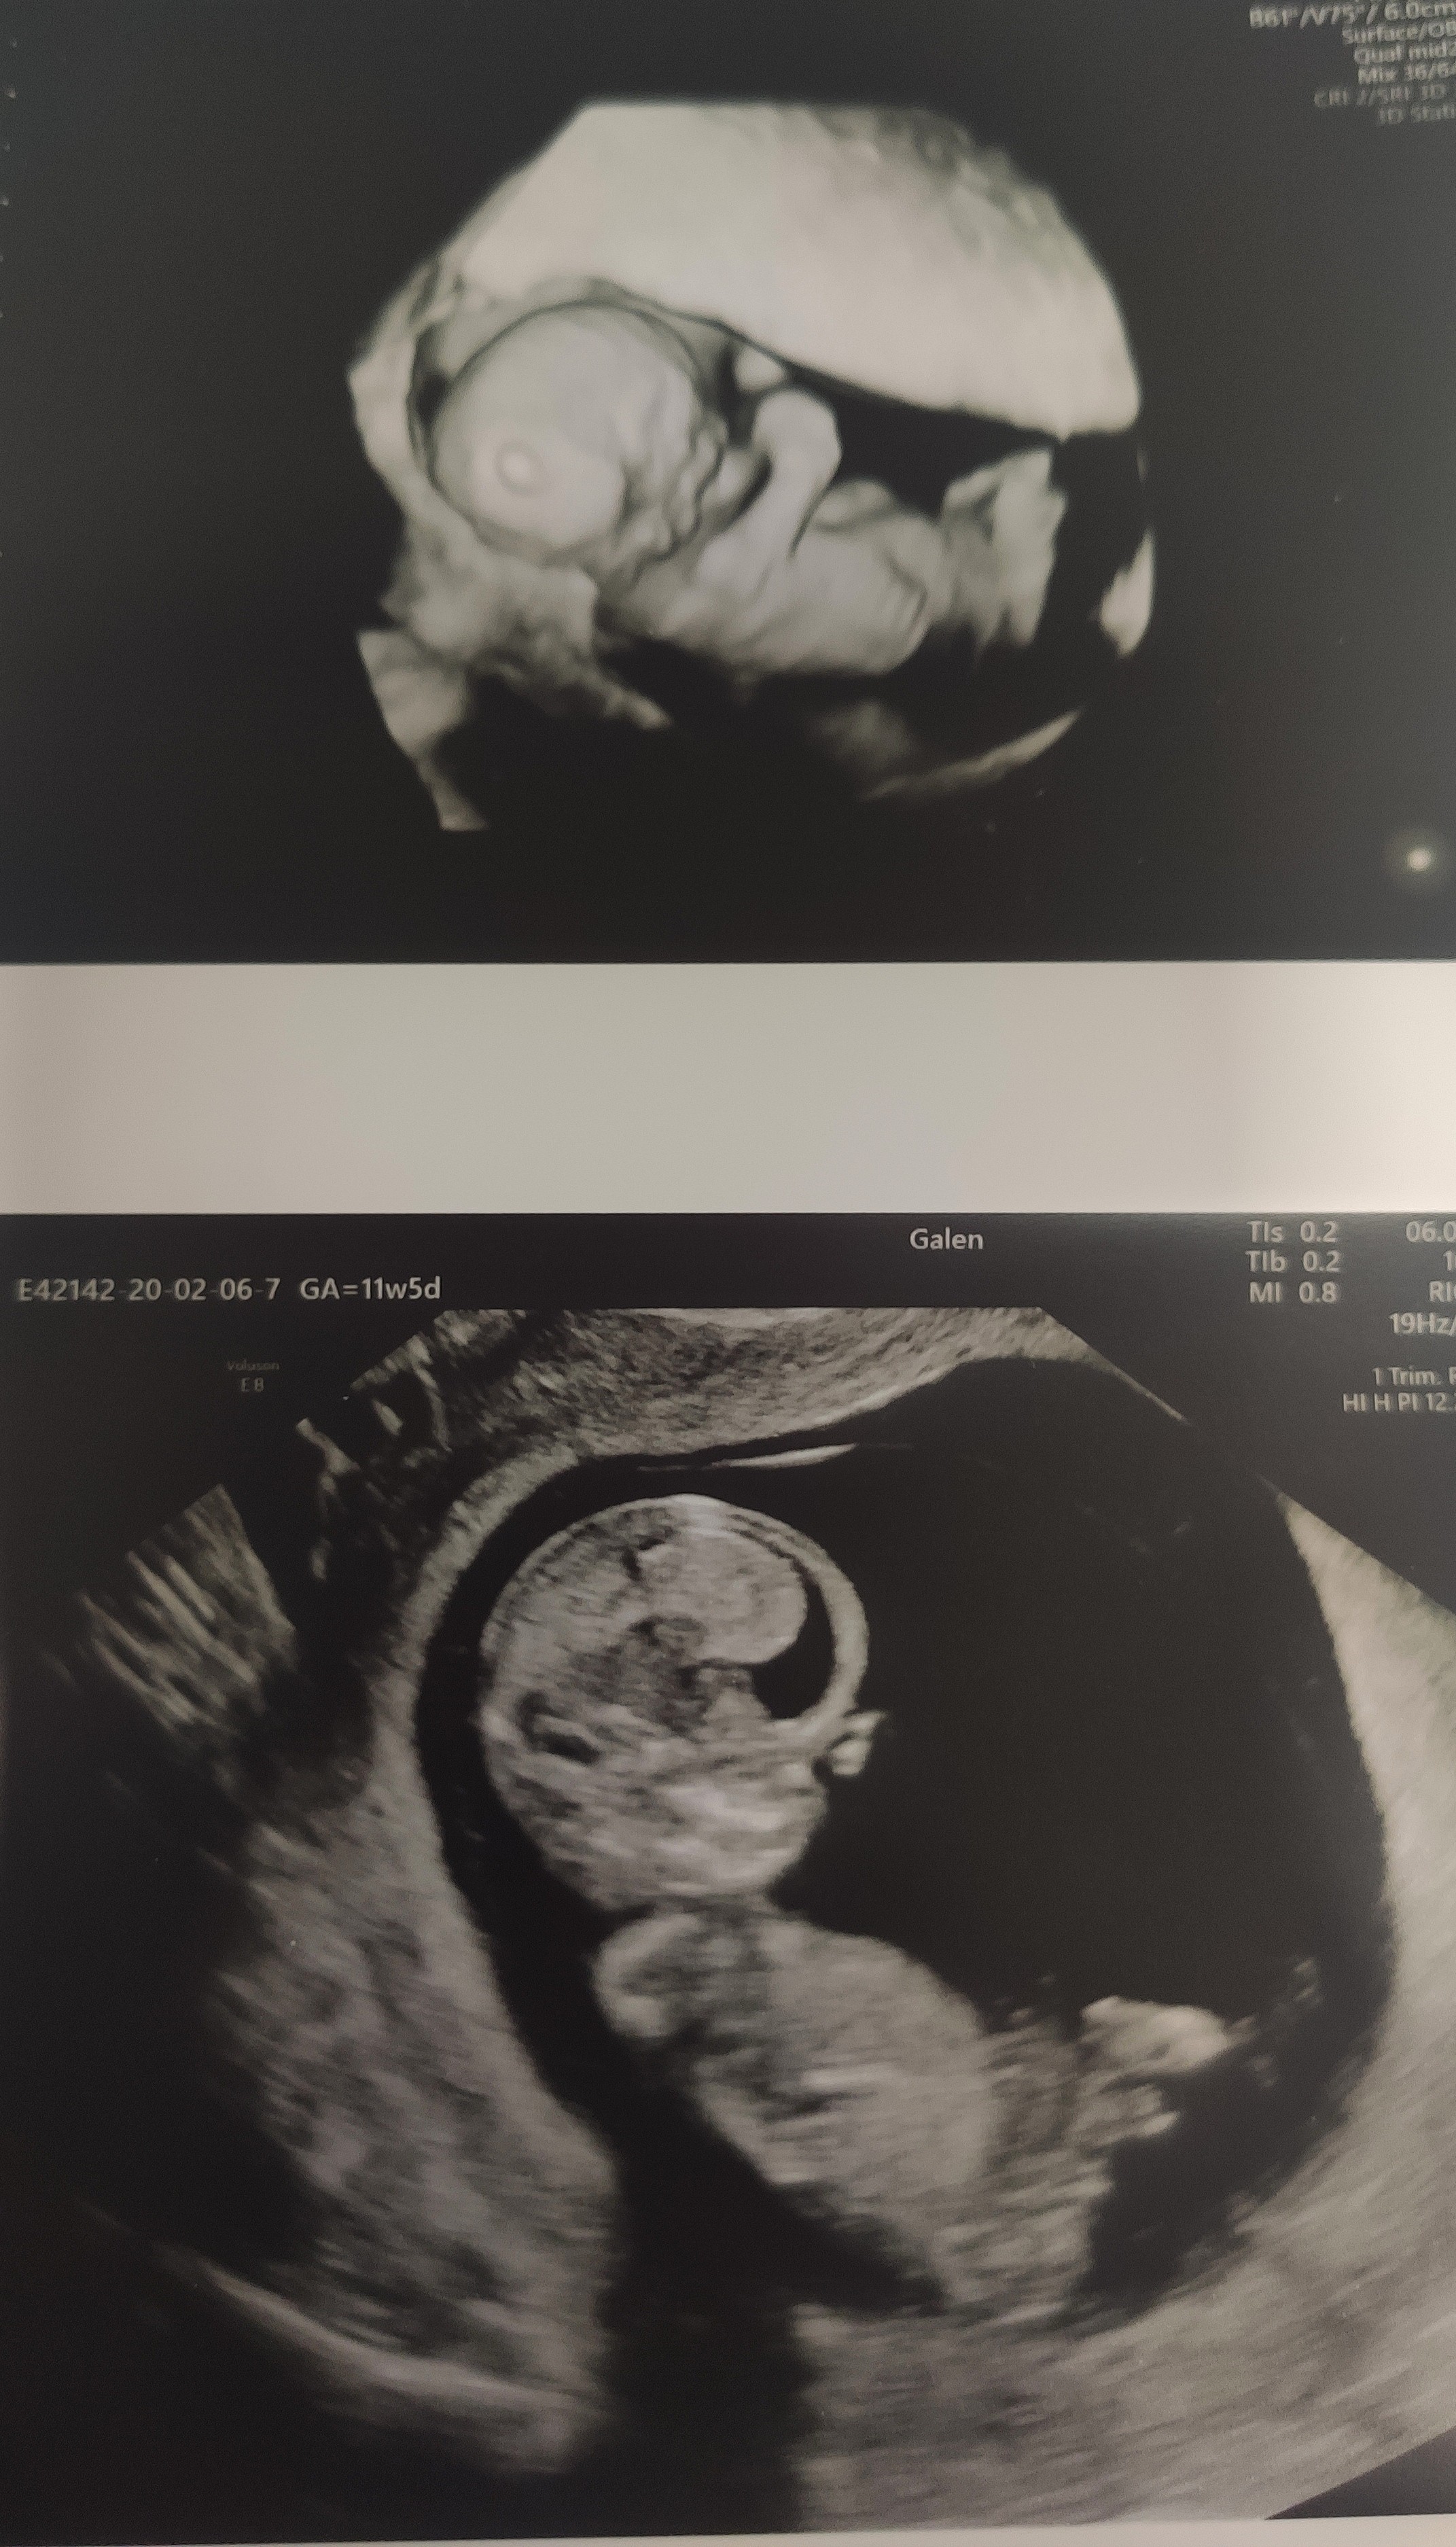

ale dobra, tylko spokój mnie uratuje... Dziś miałam kontrolę, z dzidziusiem wszytko ok, dziś mamy 11TC+5 I dzidziuś ma 5.23 cm ☺ także rośniemy.